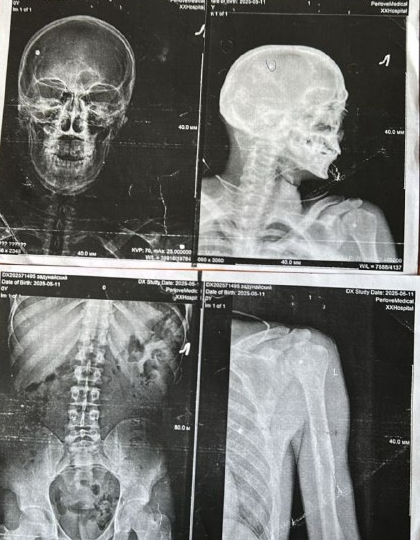

Этот кейс — наглядный алгоритм для тех, кто получил тяжелое ранение и никак не может получить заветное списание. В нашей истории военнослужащий получил тяжелые последствия военной травмы: поражение нерва с парезом кисти и другие осложнения. По видимым причинам это не являлось автоматическим основанием для увольнения. Потому что факт травмы и её реальные последствия для службы — это не одно и то же. Нужно было перевести медицинские диагнозы на язык статей Расписания болезней. Если вы в похожей ситуации, где последствия травмы игнорируются, этот разбор документа покажет вам, как должна выглядеть победа. С какой проблемой пришел военный К нам обратился контрактник. В апреле 2025 года он получил минно-взрывную травму. Были множественные слепые осколочные ранения в области плеча, перелом челюсти. После лечения остались стойкие последствия: рука работала плохо, кисть была ослаблена, беспокоили боли. В части ему давали понять, что раз он ходит и держит оружие второй рукой — служить может. Е